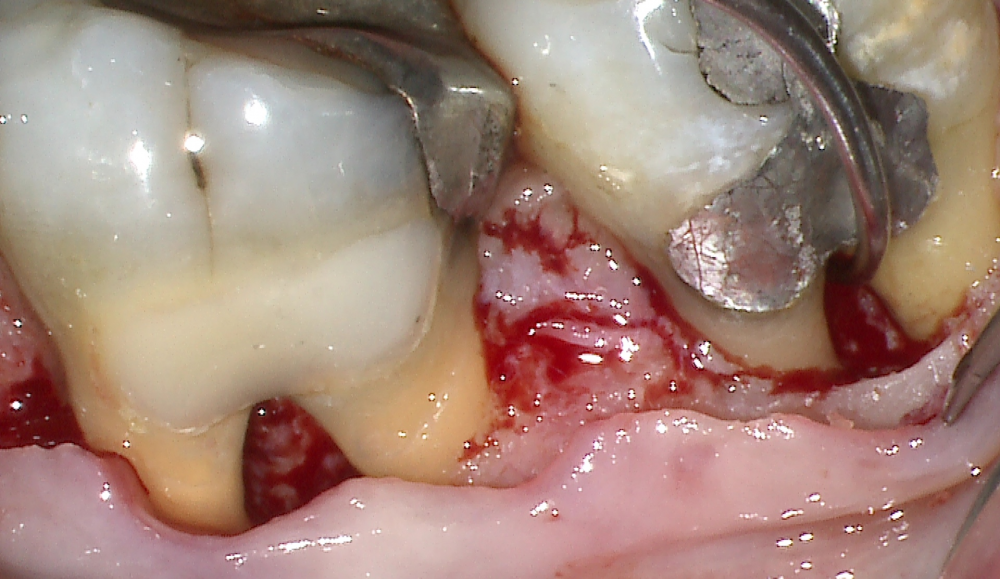

This Advanced Training Workshop will face the most challenging clinical problem in dentistry: the treatment of molars with furcation involvement. The “furcation dilemma” is still an open question with some clear answers and many dark sides. The aim of this 4-day full immersion workshop is to discuss the non-surgical and surgical approaches to give clinicians predictable solutions for the treatment of teeth with furcation involvement. The course will be empowered with ample discussion on the anatomic and diagnostic parameters to set a treatment plan. The “core” of the workshop will focus on detailed description of surgical concepts, surgical techniques, clinical tips, complications and failures. Lectures, 2D and 3D video demonstrations, hands-on training, practical exercises on simulators, and case discussion, will allow clinicians to upgrade their skills in the treatment of teeth with furcation involvement.

The world most renown Master on Periodontal Regeneration , Dr. Cortellini, and his Team propose this interactive course, powered by 2D and 3D video demonstrations, hands-on training, practical exercises on simulators, and case discussions, aiming at clinicians wishing to upgrade their skills in the application of Periodontal Therapy to teeth with furcation involvement. This unique, highly personalized course consists of an integrated approach designed to build and extend the competence of the practicing periodontist in managing the most challenging of the periodontal lesions through advanced concepts of treatment planning on an individual level. The clinical decision of saving or replacing teeth with furcation involvement will be debated and supported by scientific evidence and clinical experience.